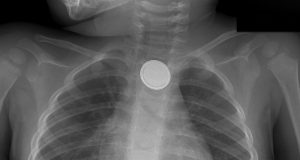

Extraen médicos monedas, uvas y figuritas de plástico del estomago de...

Ingesta de cuerpos extraños y sustancias cáusticas pueden causar consecuencias fatales si no se atienden a tiempo y debidamente, advierten especialistas

Monedas, uvas y corazones...